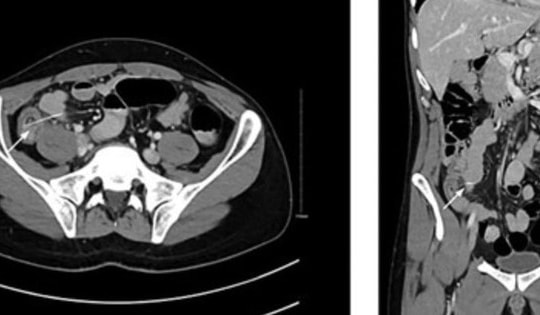

Một thiếu niên 15 tuổi phải nhập viện cấp cứu trong tình trạng đau dữ dội sau hành động bồng bột do tò mò. Thăm khám cho thấy có dị vật mắc kẹt trong cơ thể.